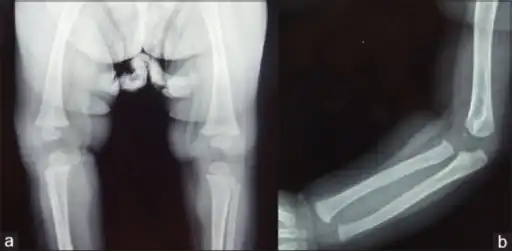

Wimberger corner sign; X-rays of (a) lower limbs (AP view) and (b) upper limbs (AP view) showing resolution of metaphyseal erosions and periosteal reaction -

a) X-ray of the lower limb (AP view) showing proximal tibial metaphyseal erosions along with periosteal reaction and (b) X-ray of the upper limb (AP view) showing distal tibial and fibular metaphyseal erosions with periosteal reaction -